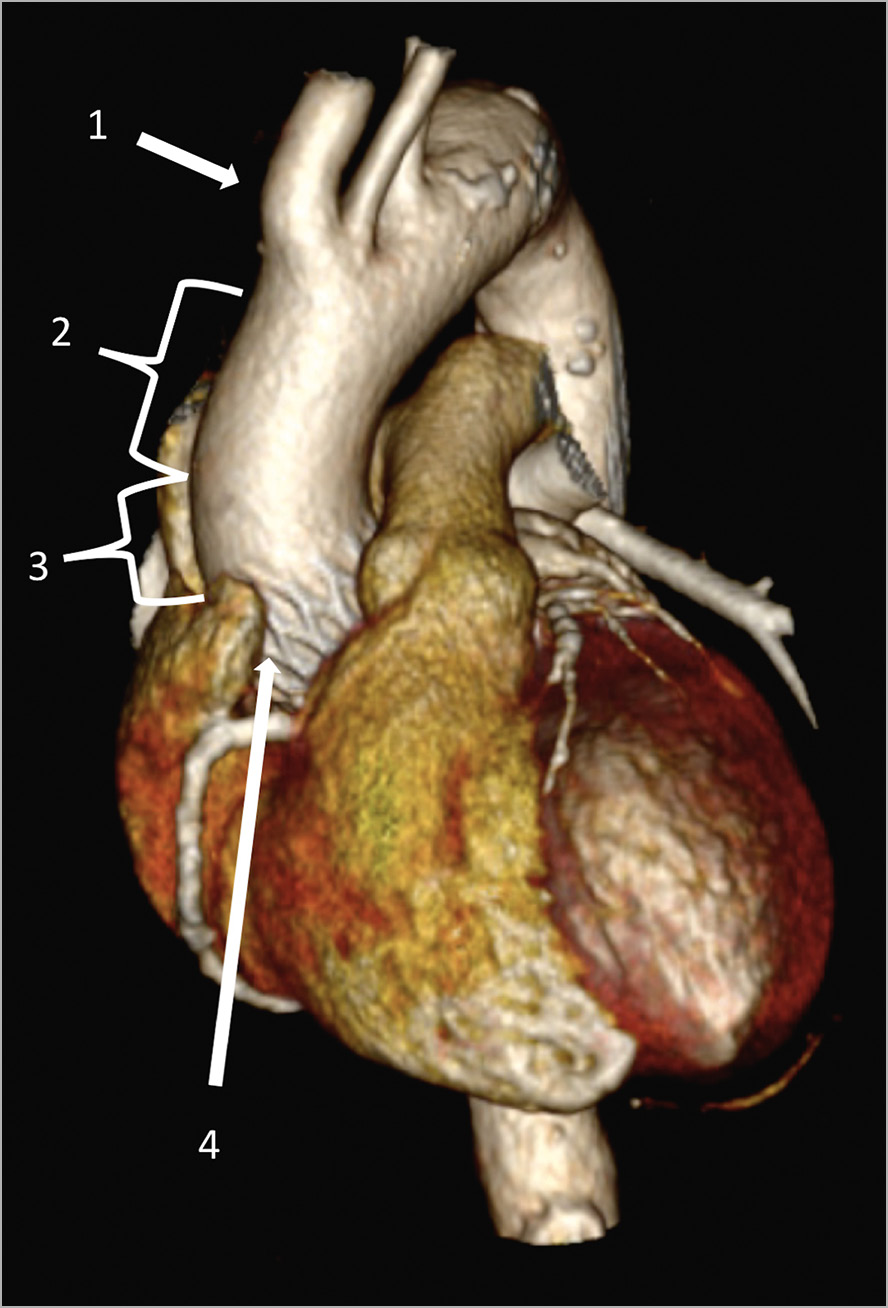

Opening of the ascending aorta after TAVI, however, may prove to be more complicated. The surgical site for aortic incision during an aortic valve replacement is generally 1 cm above the STJ in the proximity of the so-called “plica transversae aortae” or “fold of Rindfleisch”. In our study, almost half (47.9%) of the patients examined had extensive contact between the TAVI stent and the anterior aortic wall from the STJ upwards. The first site free from the TAVI stent eligible for easy cutting was approximately 2.2 cm distal from the STJ and no less than 0.7 cm. Given these findings, a high first incision for aortotomy in the presence of a TAVI device is advisable (Figure 5, Moving image 1, Moving image 2). In addition, considering the difficulty of THV detachment in the aortic root in case of strong adhesions, a longitudinal instead of transverse aortotomy could be considered, maybe with extension towards the aortic annulus.

Figure 5. Three-dimensional cardiac CT-scan reconstruction. Site for an adequate aortic cross-clamping (2) and aortotomy (3) between the ostium of the innominate artery (1) and the upper crown of the THV stent (4). CT: computed tomography; THV: transcatheter heart valve